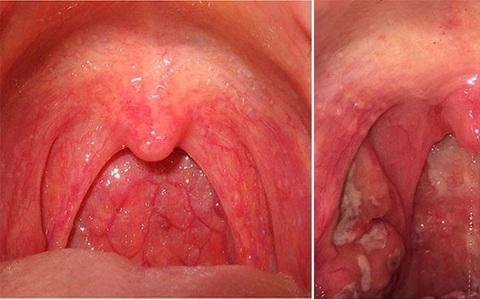

Viêm họng, viêm amidan, viêm xoang thường gặp có thể tự khỏi nếu sức đề kháng tốt và tuân thủ chỉ dẫn của bác sĩ.